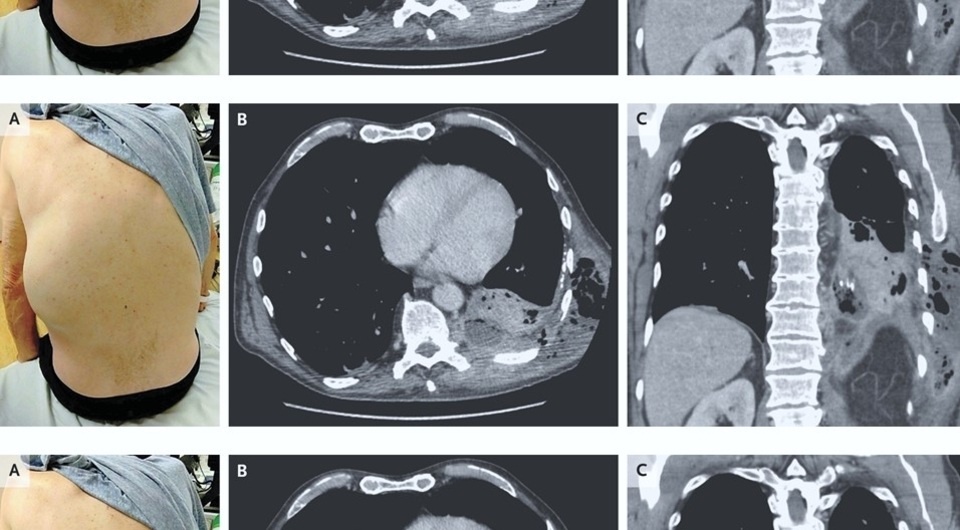

К американским врачам обратился 66-летний мужчина с хронической обструктивной болезнью легких с одышкой и кашлем в течение двух недель, а также болями в левом боку в течение пяти дней. За два дня до обращения он отметил появление и быстрое увеличение опухоли на левом боку. Обследование показало, что у пациента развилось редкое осложнение эмпиемы плевры, при котором гной не собирается в плевральной полости, а прорывает париетальную плевру и распространяется в соседние области. У мужчины он попал на левую заднюю боковую стенку грудной клетки. Случай описан в The New England Journal of Medicine.

Adeoluwa Ayoola and Kreshnik Zejnullahu / The New England Journal of Medicine, 2025

При первичном осмотре Адеолува Айоола (Adeoluwa Ayoola) и Крешник Зейнуллаху (Kreshnik Zejnullahu) из Калифорнийского университета выявили у пациента ослабление дыхания у основания левого легкого, а также болезненное образование на спине с левой стороны. Компьютерная томография грудной клетки показала уплотнение левой нижней доли, которое связали с небольшим многоочаговым плевральным выпотом, содержащим газ. Пациенту провели небольшую операцию и дренировали скопление гноя в грудной стенке. Больной прошел длительный курс антибактериальной терапии, и в течение шести месяцев его состояние нормализовалось.